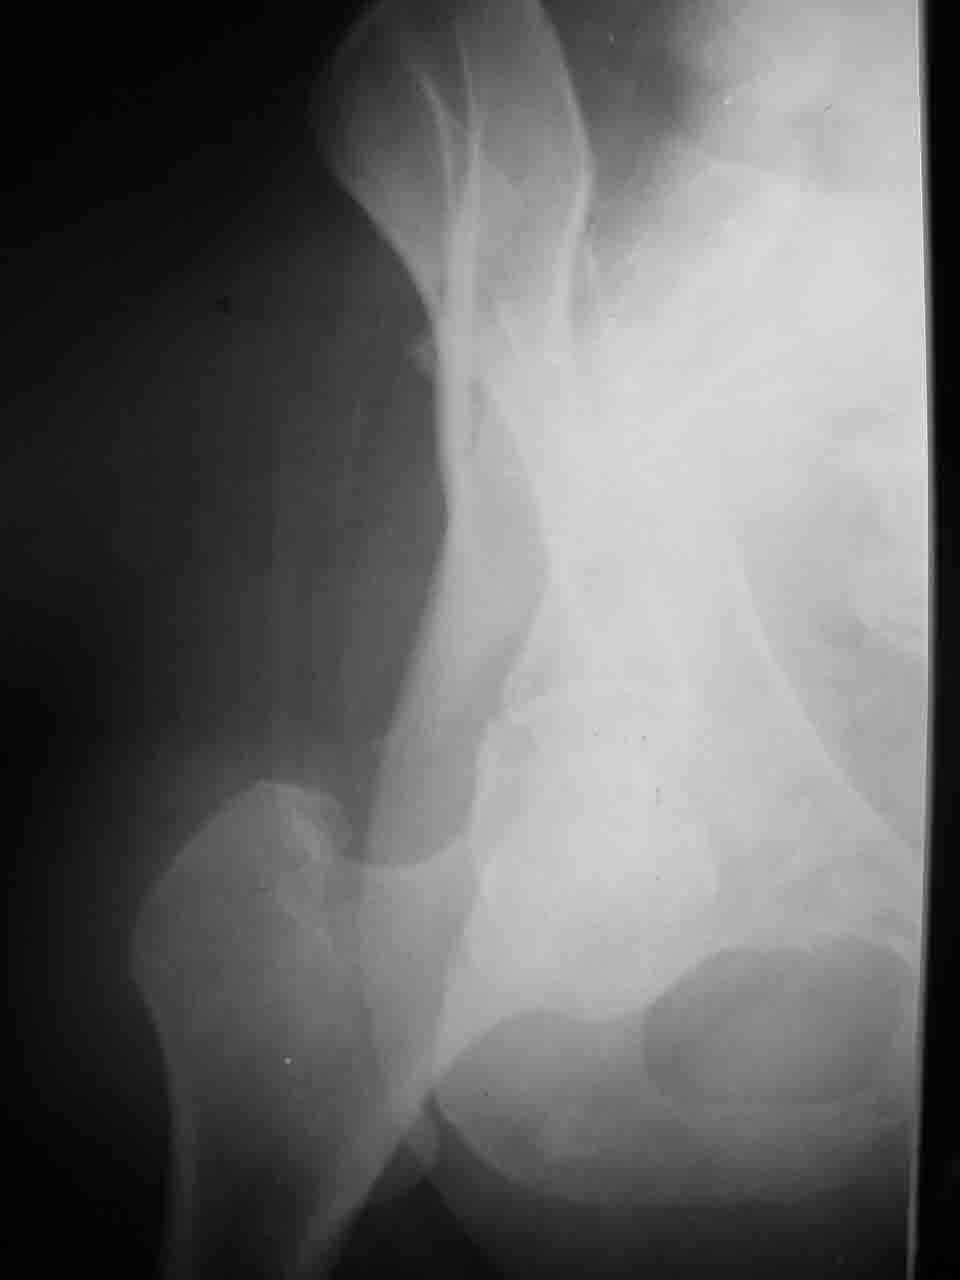

Уважаемые коллеги,43 летний мужчина, попав в автоаварию 13.10.2004, получил оскольчатый перелом обеих колонн левой вертлужной впадины.

На рентгенограммах - высокий двухколонный перелом вертлужной впадины с нарушением конгруэнтности, имеется обратная клиновидность суставной щели.